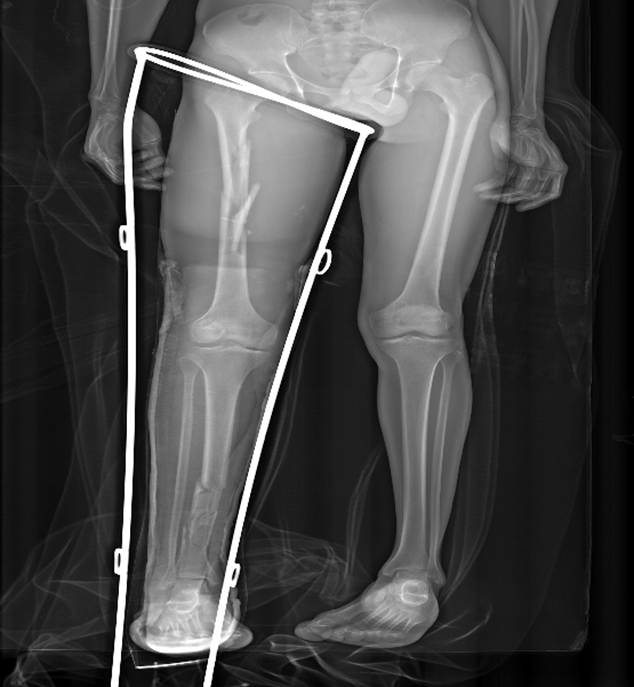

Two views are needed (AP and lateral,joint above and below included). A Thomas splint should be applied BEFORE X-ray. Exclude neck of femur fractures which occur in 10% of femur shaft fractures.

- A Thomas splint must be applied to all femur shaft fractures before X-rays (reduced blood loss, pain and FES).